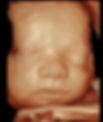

Show-Me Baby

Ultra HD Images

These images are property of Show-Me Baby Ultrasound.

All images were captured during Show-Me Baby Ultrasound Sessions.